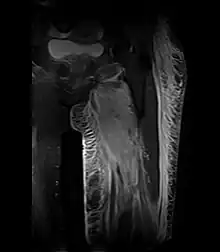

Coronal fat suppressed STIR image demonstrating enlargement and increased signal in the left adductor muscle group with associated subcutaneous edema in a patient with diabetic myonecrosis.